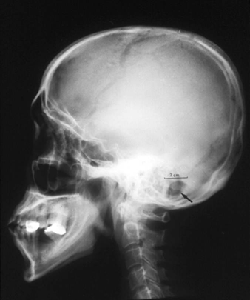

従来の脳外科手術では、腫瘍や血管の異常など病変のある部位に到達するために、頭の骨を大きく開ける必要がありました。しかし、鍵穴手術では直径1〜3センチほどの小さな開口部を設け、そこから顕微鏡と細い専用の器具を挿入して手術を行います。わずかな開頭からでも十分な視野を確保できるよう、顕微鏡の角度や照明、骨の削り方などに高度な技術が用いられます。

この「鍵穴のように小さな開頭」が、手術名の由来です。